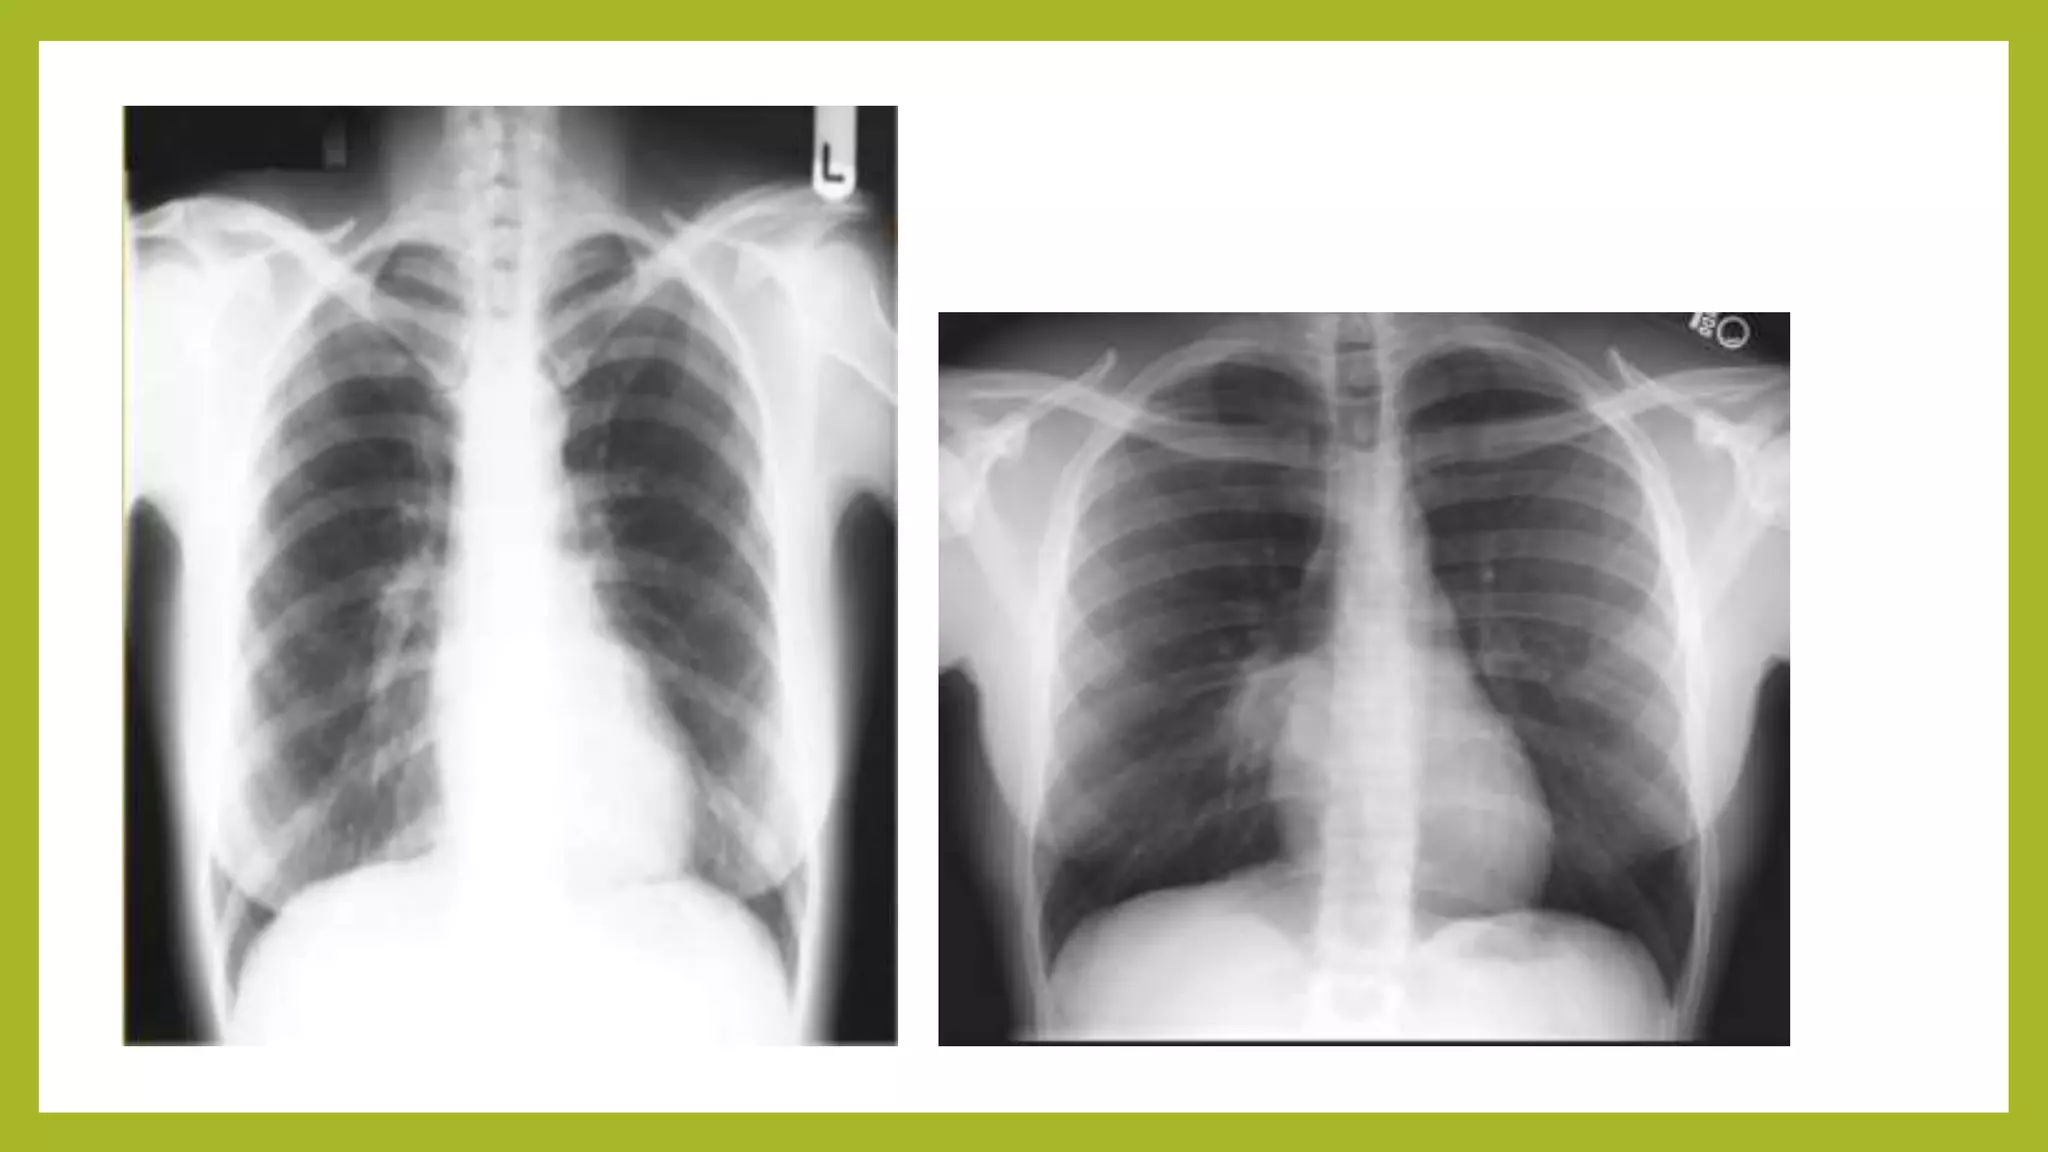

The document provides guidance on approaching and interpreting chest x-rays (CXR). It outlines steps to check the name, date and quality of the film, systematically scan the CXR looking for abnormalities, and determine if the lungs appear too white or black. Specific signs are described to help localize abnormalities, including the cardiac silhouette sign and pleural effusion signs. Examples are given of respiratory distress syndrome, tetralogy of fallot, transposition of great arteries, and total anomalous pulmonary venous return. The take home message is to summarize positive findings, compare to prior CXRs if available, and confirm findings with a radiologist.